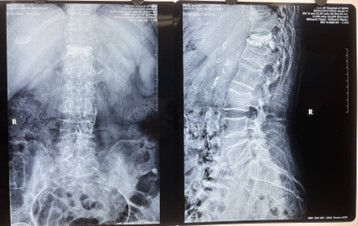

對(duì)比一些9英寸的平板C形臂,普愛(ài)醫(yī)療PLX119C大平板C形臂,30CM*30CM想(30CM*30CM)的成像范圍,一次性可成像5節(jié)腰椎,有效減少小視野C形臂難以一次性確定傷椎,可能需要進(jìn)行多次拍攝的問(wèn)題,使得手術(shù)效率更快、更準(zhǔn)確。